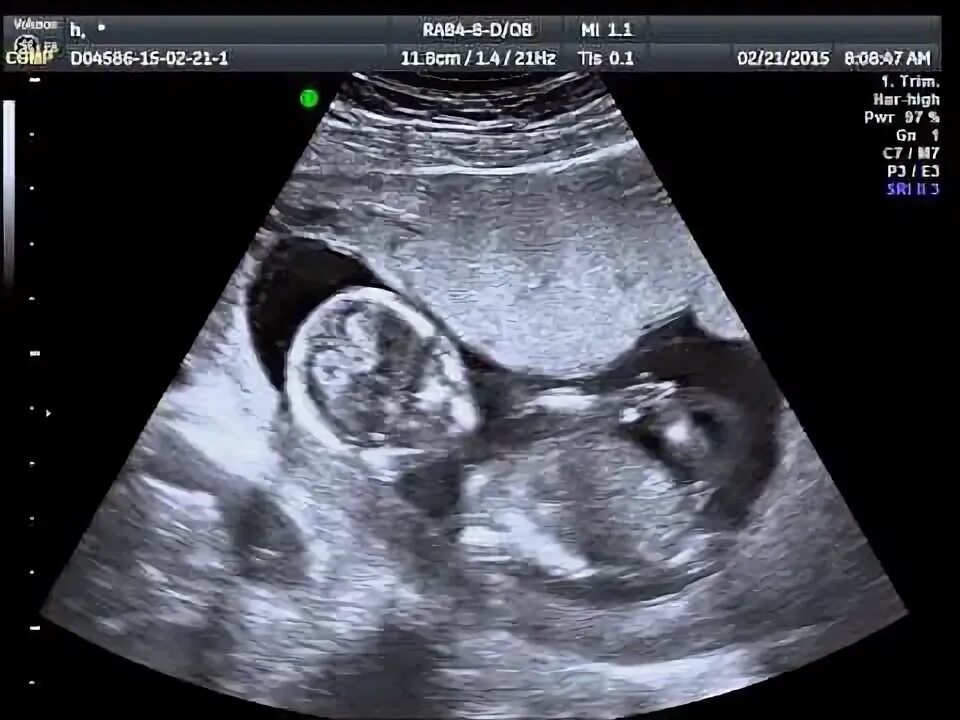

12 недель тошнит